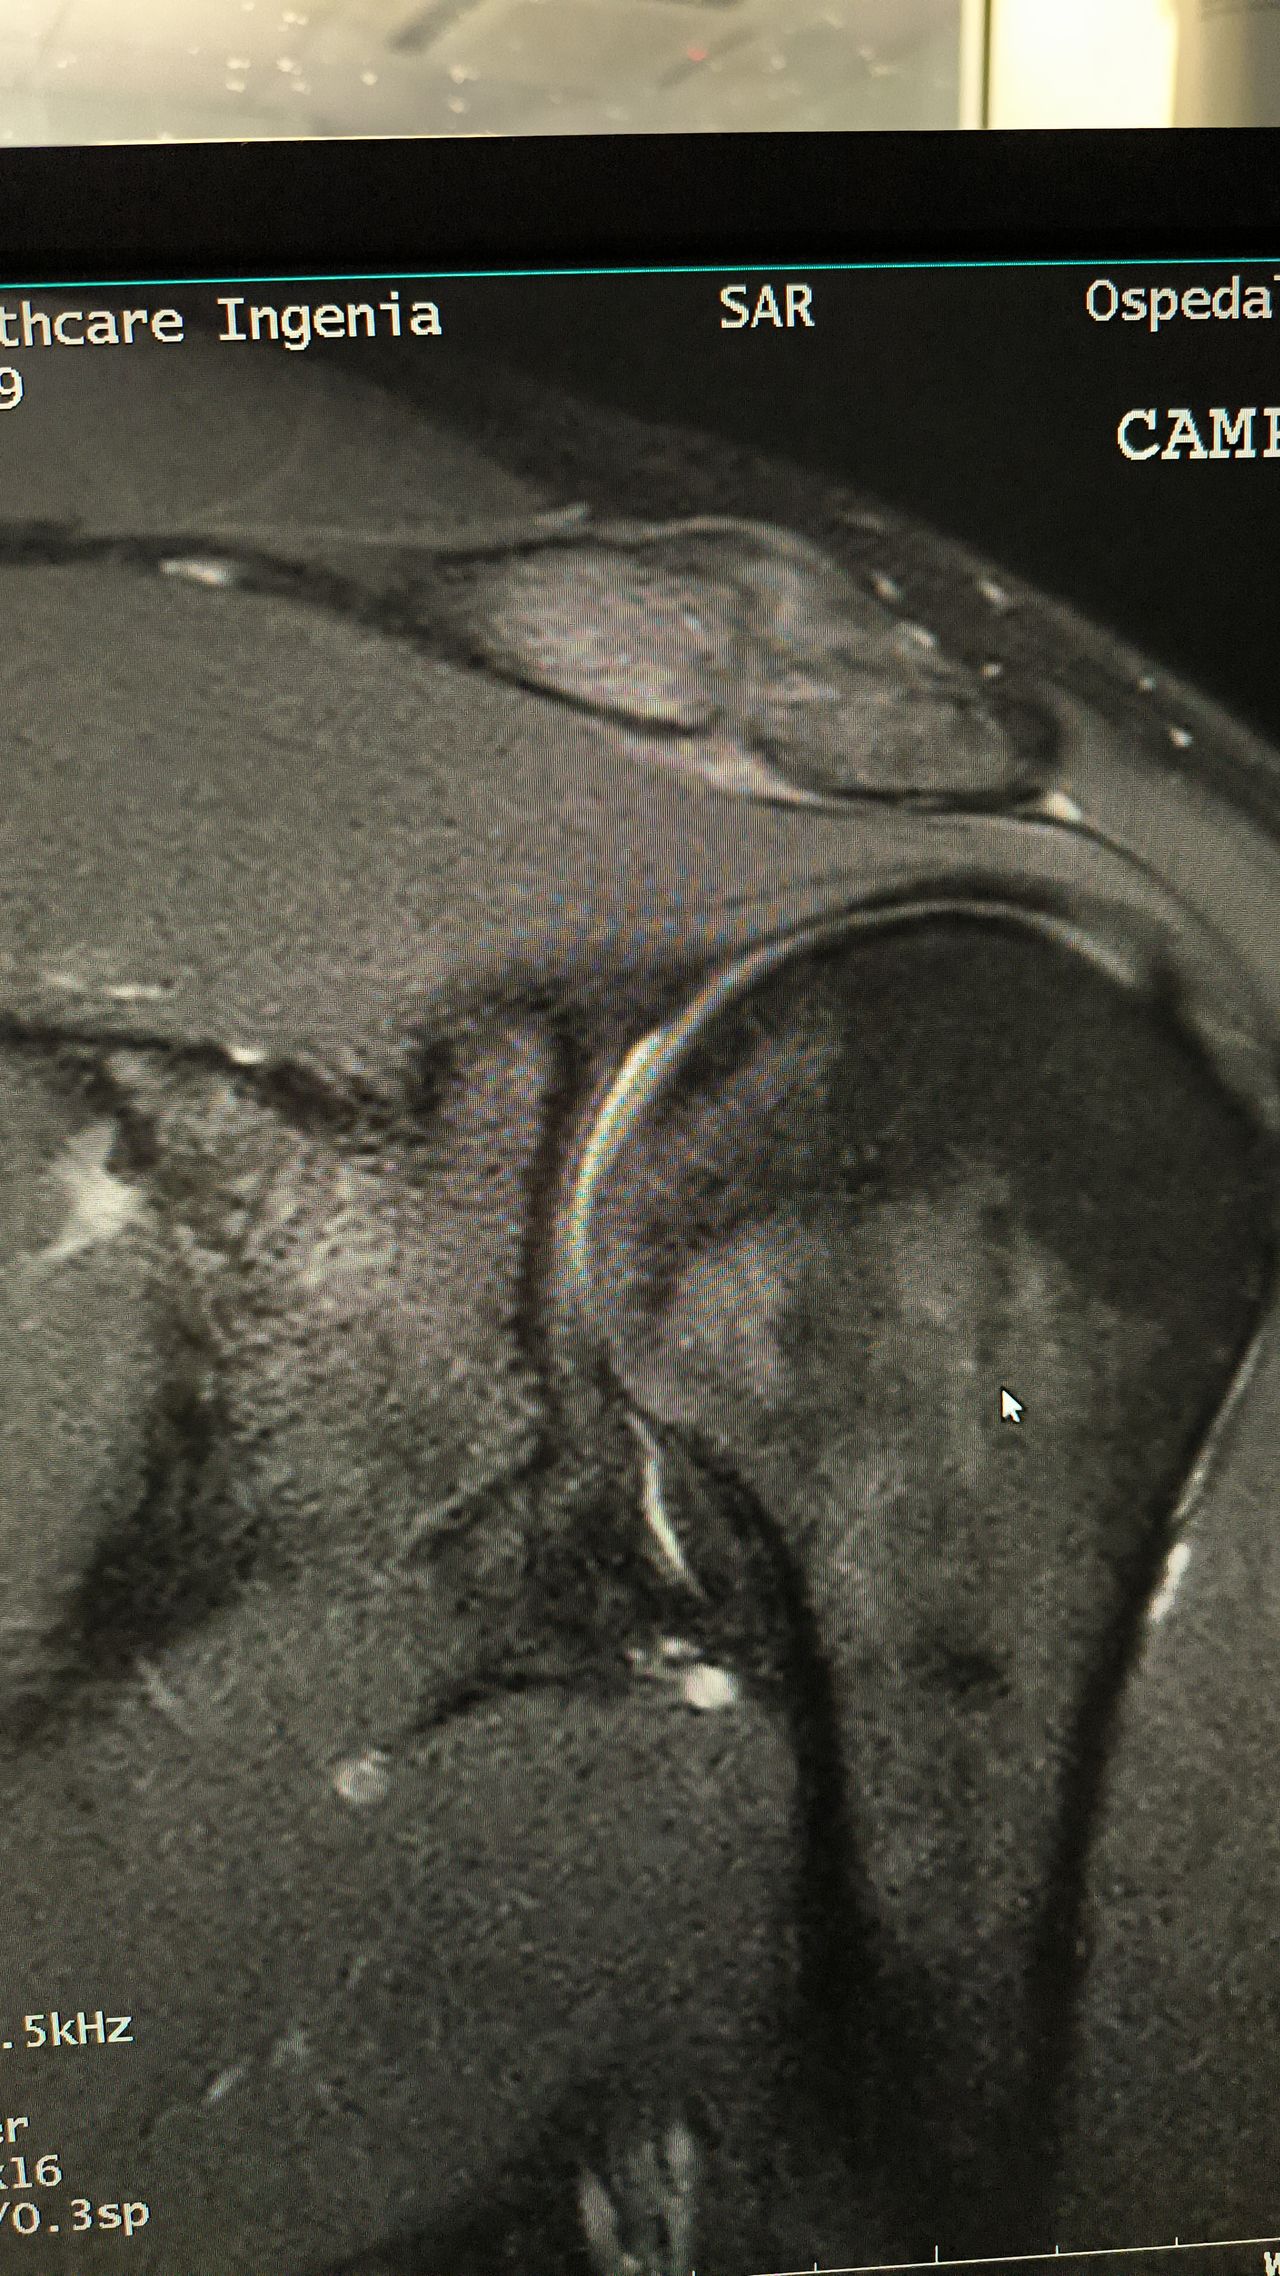

Foto e video

• Risonanza magnetica

150 €